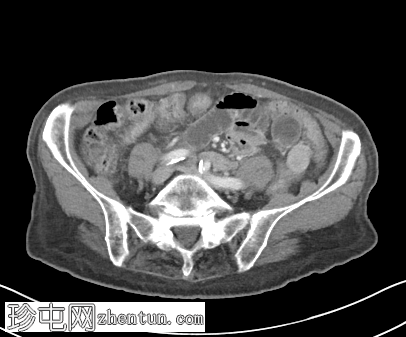

冠状位增强扫描(门静脉期)

可见右侧股疝嵌顿,右侧股静脉受压,输出小肠袢塌陷,输入小肠袢扩张。可见中等量周围游离液体。无缺血征象。右侧努克氏管向内侧移位。疝颈位于腹壁下动脉起始部和腹股沟韧带下方。

肝脏可见多个小囊肿。左侧肾上腺肿大,内含低强化结节。

股总静脉受压、疝颈狭窄、女性、努克氏管向内侧移位、疝颈起源于腹壁下动脉起始部和腹股沟韧带下方等表现,更倾向于股疝而非腹股沟疝。